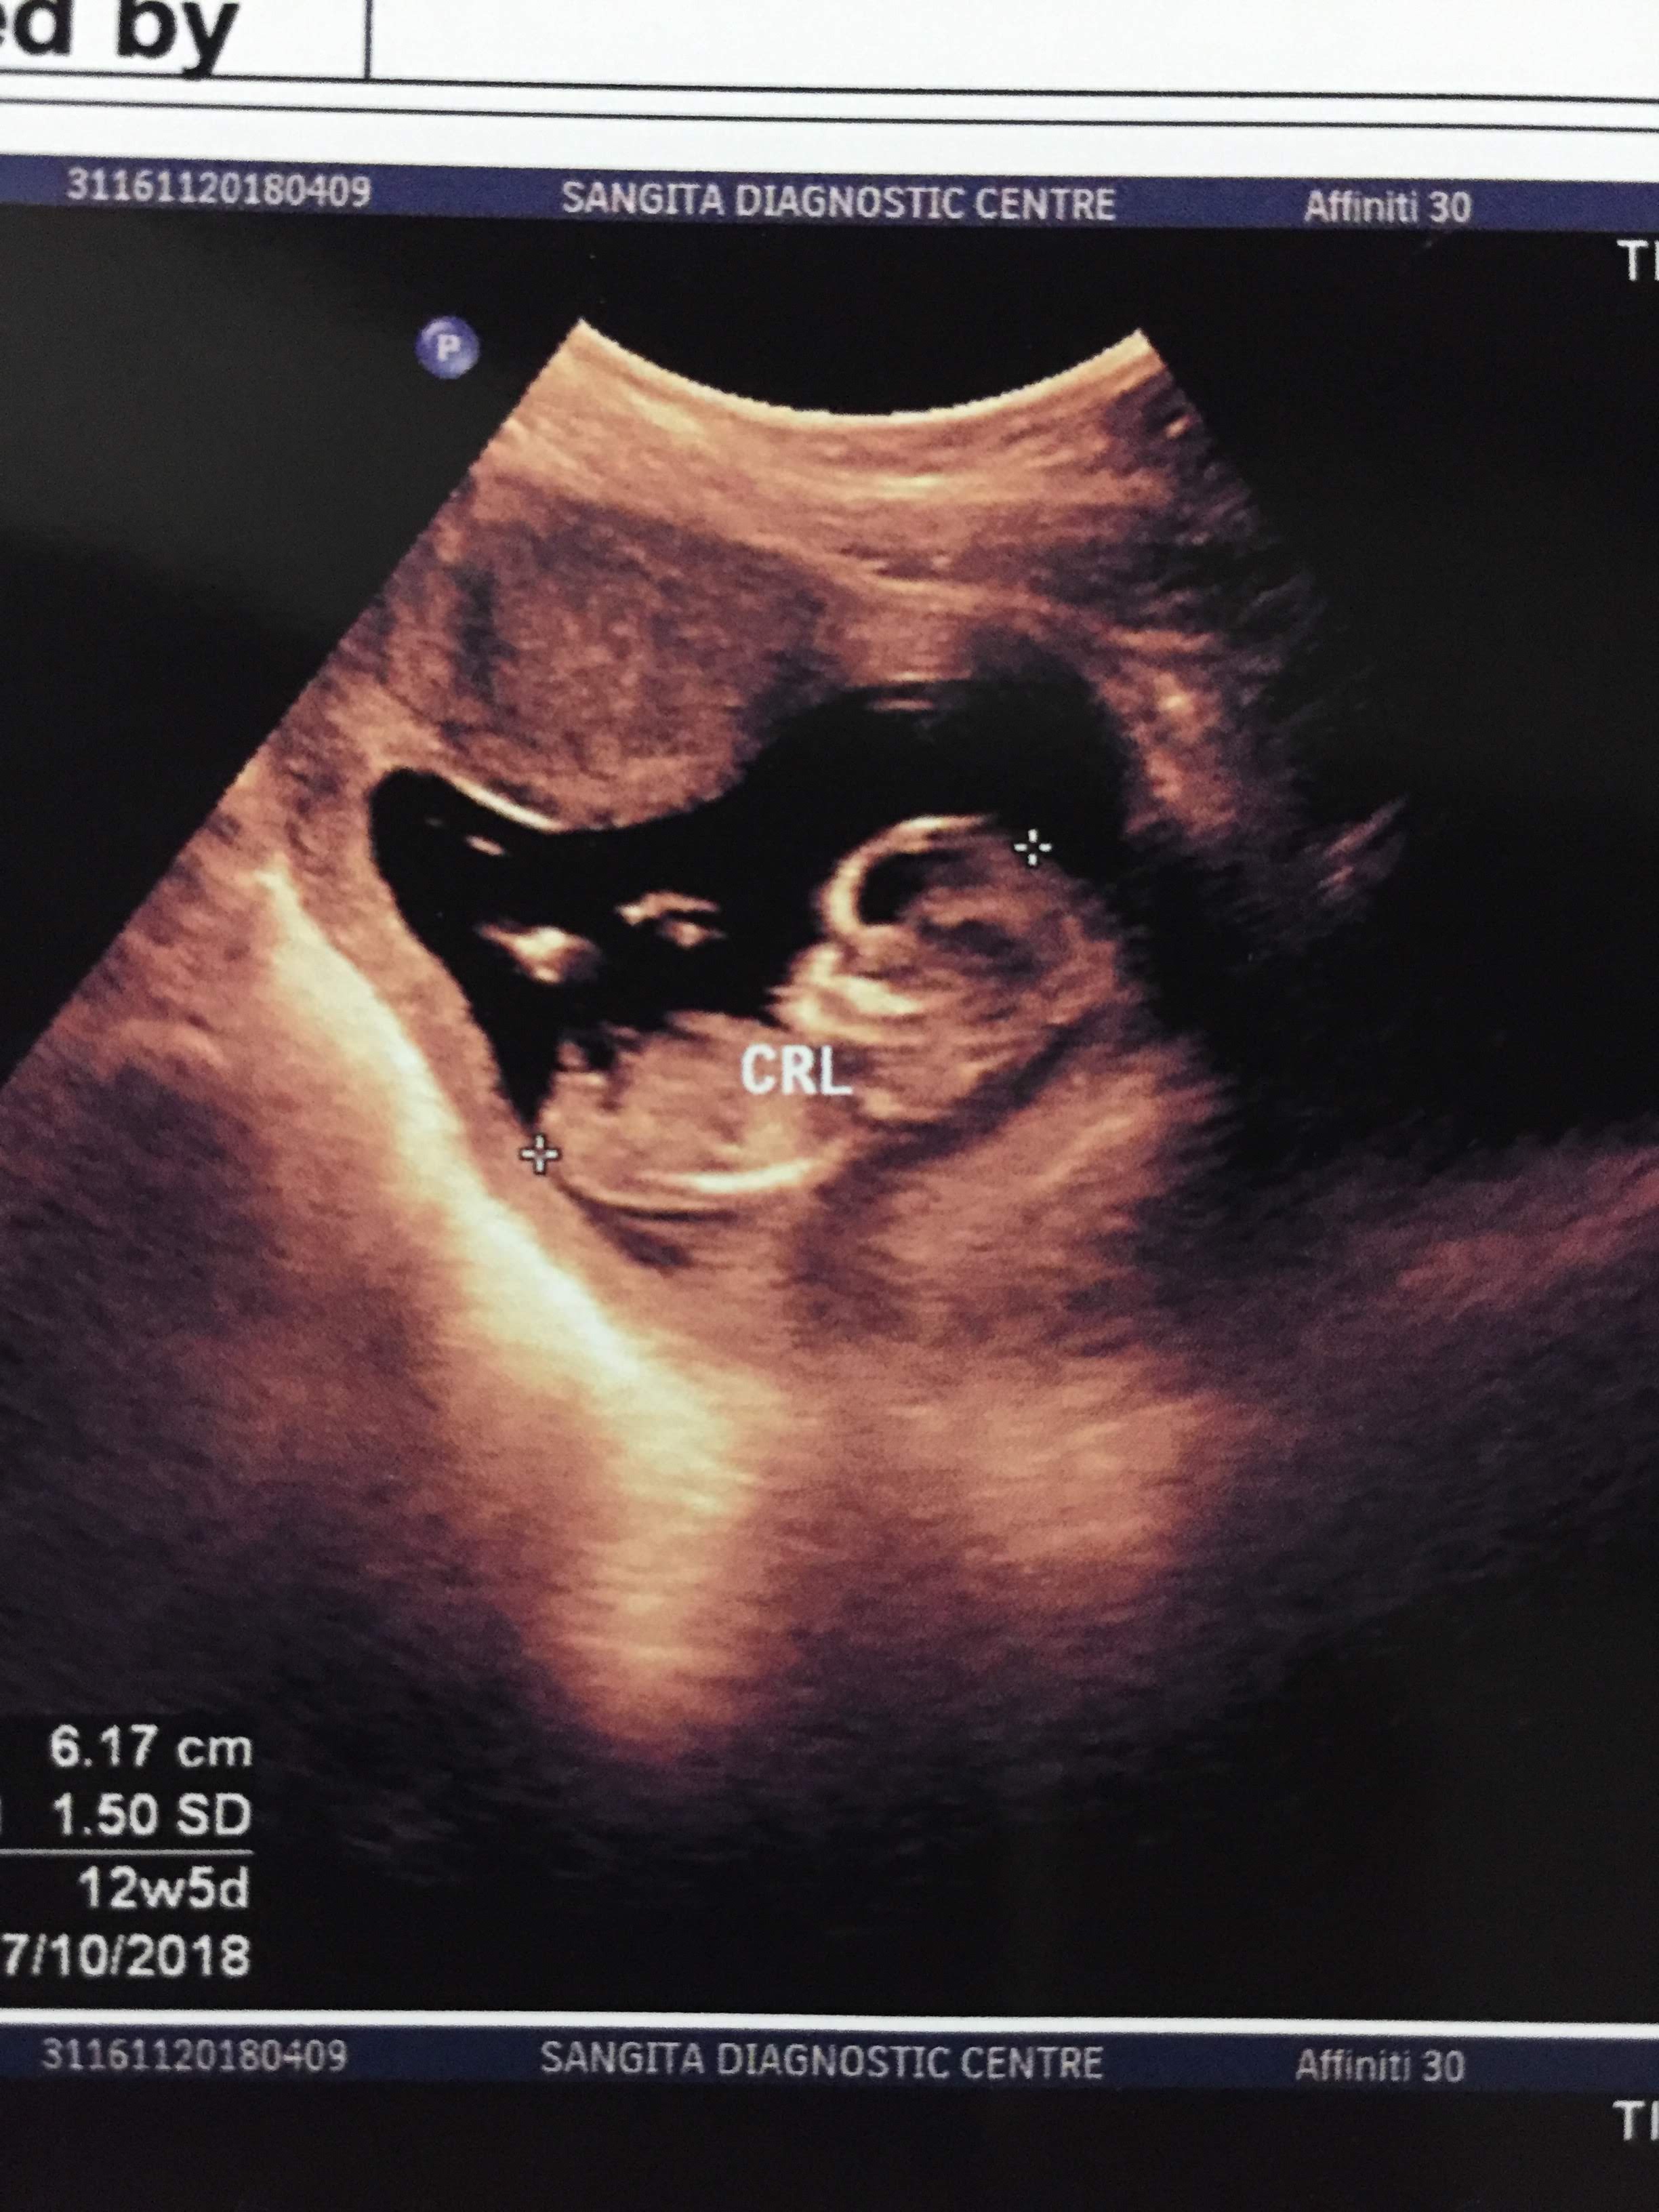

12weeks 5 Days scan

Not the best pics but first pic looks maybe girly however the third one looks like a boy nub. Really not the best pics for nub guessing.

12 weeks 5 days